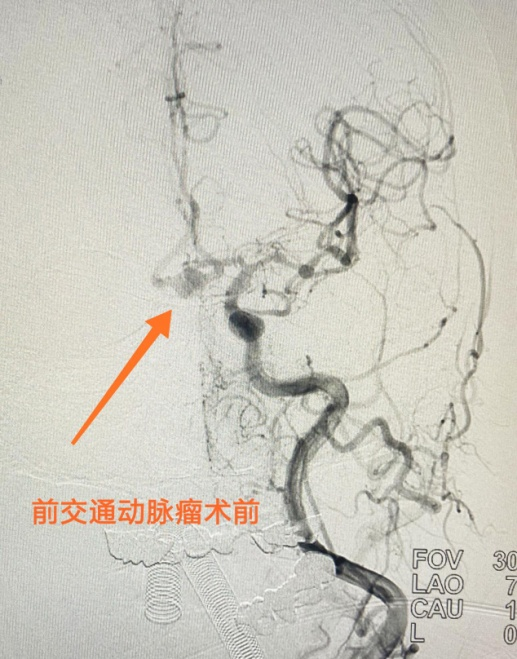

拆除“顱內(nèi)炸彈”與死神在賽跑

76歲的周某經(jīng)歷了她人生中最嚴(yán)峻的生死考驗(yàn)——活動(dòng)中突發(fā)劇烈頭痛,在當(dāng)?shù)乜h醫(yī)院診斷為蛛網(wǎng)膜下腔出血,被緊急轉(zhuǎn)至我院...